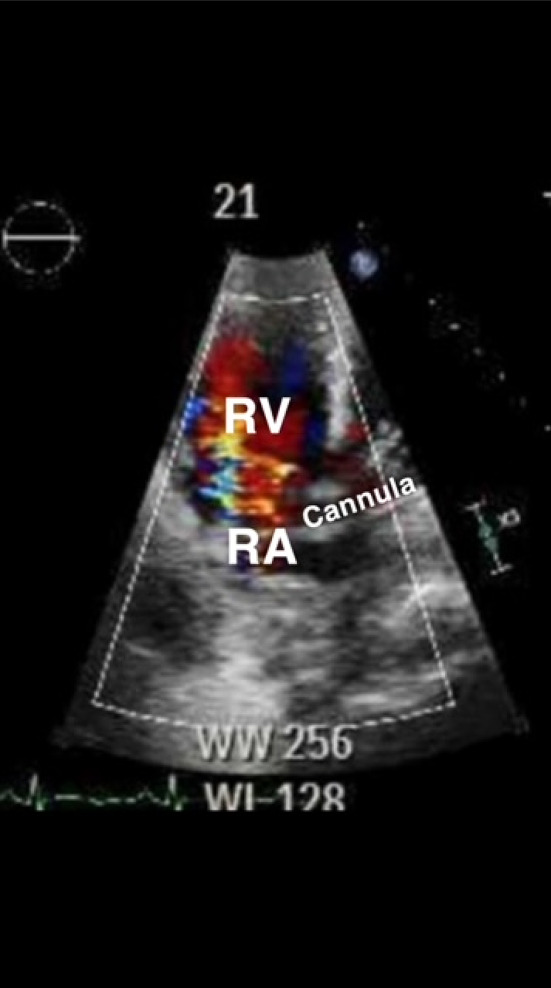

背景:护理点超声(POCUS)已成为重症监护室(ICU)评估危重病人的主要方法。ECMO 患者在重症监护室长期住院期间很容易出现并发症,包括插管错位,从而造成不良后果。尽管有关超声波在 ECMO 患者身上的作用的文献很多,但在插管错位的识别方面,还缺乏放射成像与超声波的直接比较:作者发现了四名通过 POCUS 发现插管错位的患者,而这些患者在常规放射成像检查中被漏诊。插管错位的识别和纠正改变了他们的 ECMO 疗程:本系列病例是首次在文献中证明超声在 ECMO 插管错位方面可能优于放射影像。有必要对此进行进一步研究。

Background: Point-of-care ultrasound (POCUS) has become a mainstay in the evaluation of critically ill patients in the intensive care unit (ICU). ECMO patients are susceptible to complications during prolonged ICU stay, including cannula malposition, which has deleterious consequences. Although the literature surrounding utility of ultrasound on ECMO patients is expansive, direct comparison between radiographic imaging versus ultrasound for identification of cannula malposition is lacking.

Case presentation: The authors identified four patients with cannula malposition discovered through POCUS that was missed on routine radiographic imaging. Identification and correction of malposition changed their ECMO course.

Conclusion: This case series is the first in literature demonstrating that ultrasound may be superior to radiographic images for ECMO cannula malposition. Further investigation into this subject is warranted.